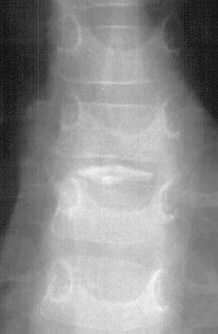

Patient is a 4 year old male who developed the insidious onset of neck pain and stiffness 4 days prior to admission. Over the intervening period, the patient suffered from worsening of his symptoms which led to increasing irritability and difficulty sleeping. On the day of admission, he was seen by a local pediatrician for severe neck pain. It was observed that his head was in a fixed position just slightly right of midline. The patient's past medical history was remarkable for two recent self-limited episodes of hives and urticaria on his trunk and extremities that was treated with prednisone. There was vague history of remote trauma about one month previously when the patient had been "horsing" around with his brother. The child had no evidence of a viral prodrome, constitutional symptoms or travel history. He was sent to a local hospital where radiographs of the cervical spine demonstrated calcifications in the C3-4 and C5-6 intervertebral disc spaces . Neurological exam was normal. The child's pain was refractory to morphine treatment and he was transferred to A.I. for the management of his intractable pain. On arrival, his physical exam was unchanged. Blood work revealed a WBC count of 12.7K with 75% PMNs and an ESR of 80. Radiographs of spine showed the presence of an addition calcification in his thoracic spine . He was treated with oral valium and a soft cervical collar. Over the ensuing 24 hrs the child demonstrated marked improvement of his symptoms and was switched to motrin. He was subsequently discharged.

Pathophysiology appears to involve calcification of the nucleus pulposus. The annular ligament is spared. The calcified nucleus pulposus may herniate anteriorly into the prevertebral soft tissues or posteriorly into the spinal canal. Changes have been observed in vertebral bodies, but there clinical significance is unclear.

The number of calcified discs varied from 1 to 12 (mean 1.69) . Symptomatic calcified discs are most common at C6-7. Radiologic examination shows images of calcium density in the normally radiolucent intervertebral discs. Anterior or posterior protrusion can be observed. The lesions demonstrate high density on CT and low signal intensity on MRI.